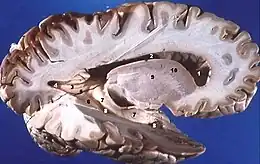

Hémisphère droit d'un cerveau humain disséqué à la suite d'une coupe sagittale, révélant la substance grise dans la partie externe et la substance blanche dans la partie interne.

Dans l'encéphale, la substance grise est située en périphérie, c'est-à-dire autour de la substance blanche. De ce fait, on dit que la substance grise définit un cortex écorce » en latin). Ce cortex est formé d'un empilement de couches de cellules nerveuses (entre 3 et 6 pour le cortex cérébral et 3 pour le cortex cérébelleux) lesquelles se différencient par le type cytoarchitectonique, la densité cellulaire et la connectivité. Autour des ventricules cérébraux, la substance grise est agglutinée en amas cellulaires qui n'ont généralement pas l'organisation laminaire des cortex : ce sont les noyaux gris centraux (thalamus, ganglions de la base, etc.).